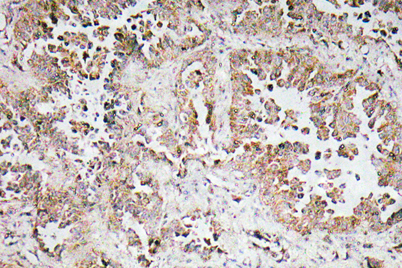

Dilutions: Western Blot: 1/500 - 1/2000. Immunohistochemistry: 1/100 - 1/300. ELISA: 1/10000. Not yet tested in other applications.

Cellular localization: Cytoplasm . Detected in cytoplasmic inclusion bodies, together with SNCA.